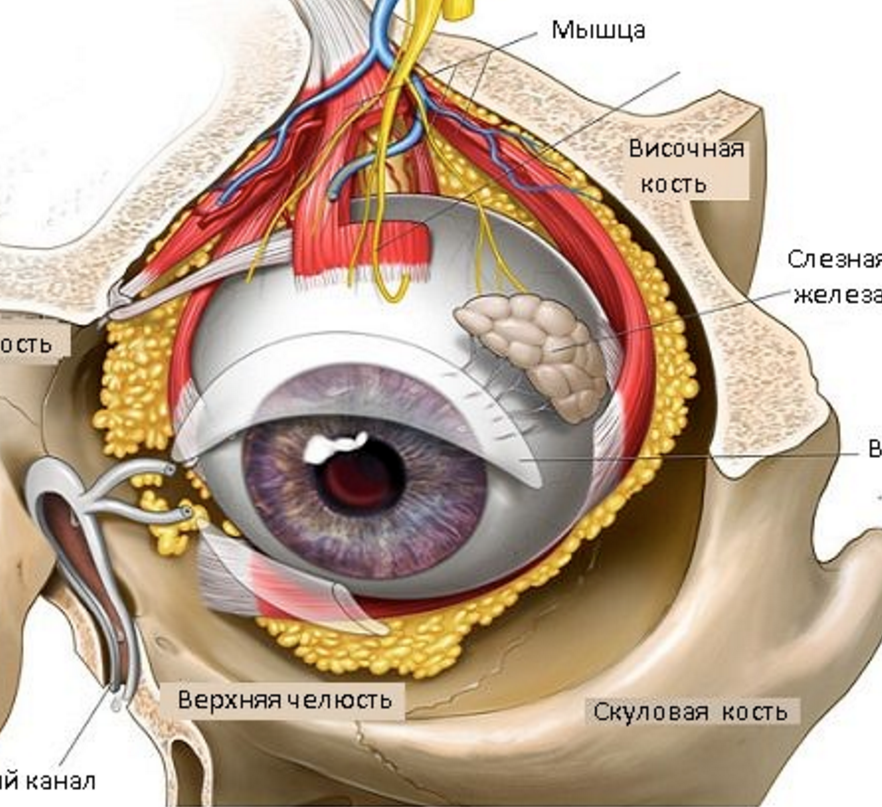

КТ-графики и изображение строения глаза